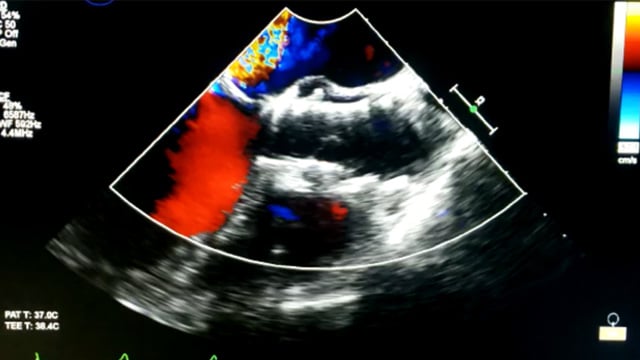

Watch this EuroIntervention image to learn how the collision of a TAV device during valve crossing in ViV TAVI can potentially cause instability or dehiscence of the sutureless bioprosthesis, contributing to severe poorly tolerated PVL.